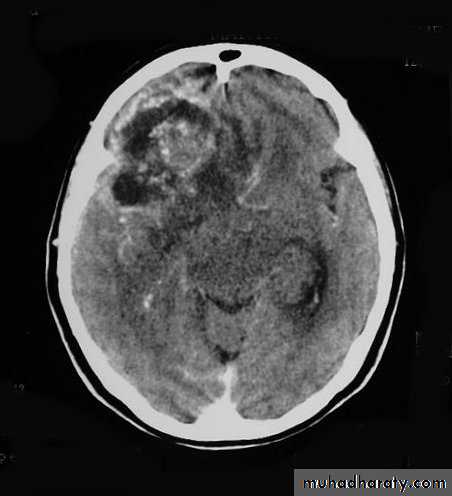

Metastatic Brain Tumours Pre contrast CT

Metastatic Brain Tumours Post contrast CT